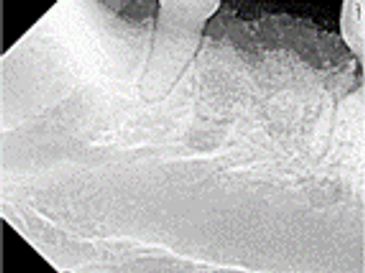

Extractions can often be complicated by severe periodontal disease, cyst formation, or unerupted teeth. Surgical ex tractions can be performed for complicated cases. Goals are to minimize bone loss. Bone graft placement can enhance new bone formation with the goal of maintaining bone height around the adjacent teeth.